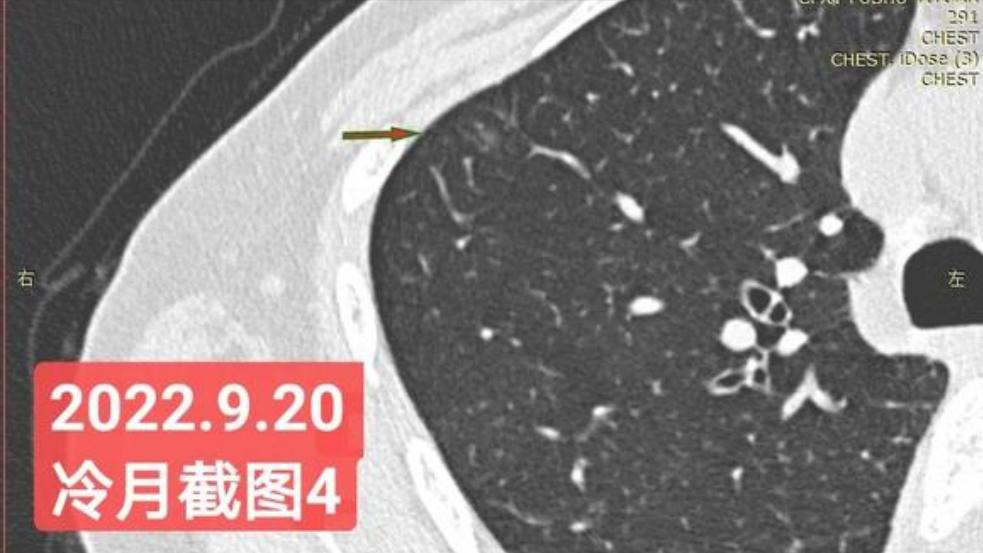

非常感谢戴主任和冷月等几位吧主的无私奉献,你们牺牲自己的休息时间,为广大患者排忧解难,你们对待病人,如同亲人一样,真的好感动!上次,在贴吧里咨询过戴主任关于我的肺结节情况,戴主任说,我右肺下叶那个结节高危。心里好害怕,距离上次CT间隔三个月,我又做了肺部CT,这次还要劳烦戴主任以及吧主们,帮我看看我的肺结节,严重吗?需要马上手术吗?

我昨天把我五次肺部CT电子版以及报告,发给了冷月吧主,昨天晚上,冷月吧主就为我截好图,发给我,非常令我感动,谢谢您冷月吧主,您辛苦了,您要多休息,不要太辛苦了。

我是21年7月做肺部CT,报告给报出0.5厘米肺结节。(但大夫说,20年就已经有那个肺结节了,因为小,报告没给报)。自发现肺结节后,吃了四个月中药,结节没有缩小,反而增大了。今年8月1日开始到现在,又吃了近两个月的蒙药了。 结节还是没有缩小,反而在增大。21年7月到现在,复查过3次肺部CT了。结节一直在增大。最近一次复查时间是2022年9月24日。

上次找戴主任贴吧咨询过,主任说我右肺下叶那个结节高危,距离上次CT,到现在三个月复查肺部CT。所以9月24日又复查做了肺部CT。